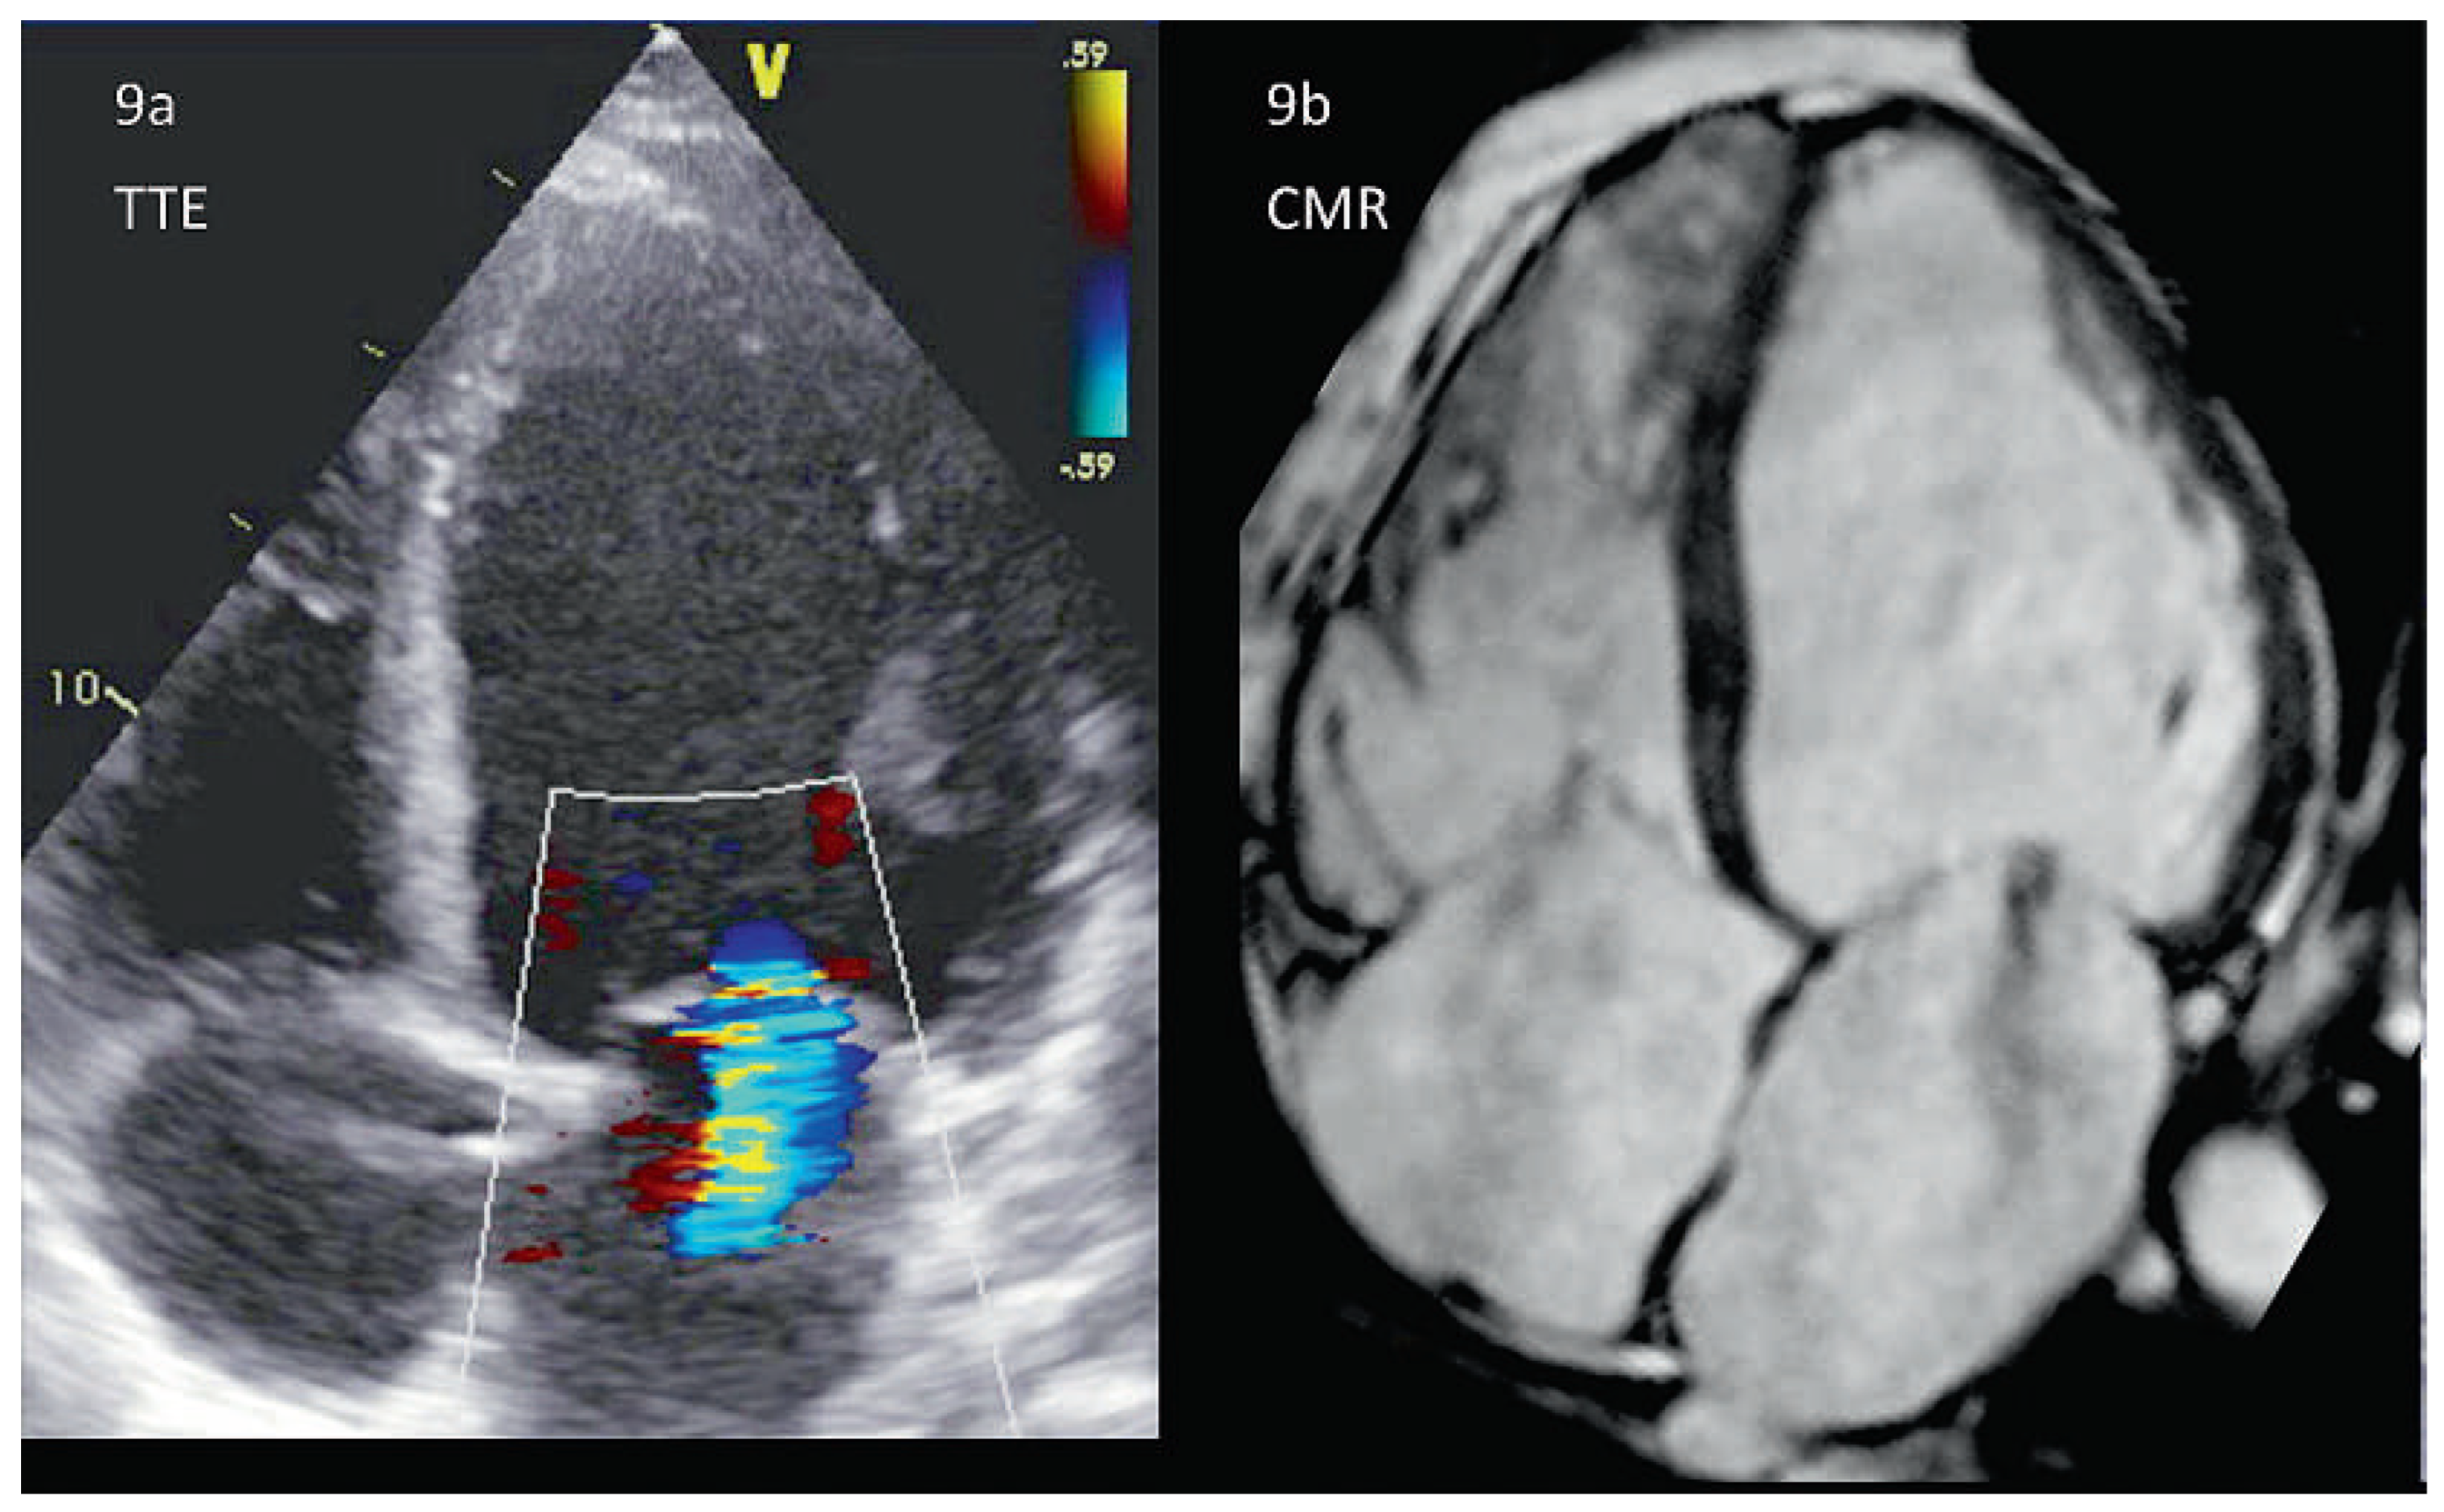

Das bevorzugte bildgebende Verfahren zur Diagnose einer durch eine KMP verursachte Mitralinsuffizienz ist die Echokardiographie [41]. Die Grösse des linken Ventrikels sowie die exakte Störung seiner Geometrie können dargestellt werden (Abbildung 9a). Ebenfalls erkennbar ist das Ausmass der Anulusdilatation und des Tetherings der Sehnenfäden. Zudem können die «tenting height» und «tenting area» gemessen werden, welche für die chirurgische Sanierung eine prognostische Aussagekraft besitzen [42]. Die Quantifizierung der Mitralinsuffizienz birgt die eingangs erwähnten Schwierigkeiten. Gewisse Formen der KMP ergeben ein typisches, in der Echokardiographie gut zu erkennendes Myokardmuster ab (z.B. Amyloidose).

Für echokardiographisch unerklärte Formen kann in einigen Fällen die CMR weiterhelfen, welche eine zusätzliche Gewebecharakterisierung erlaubt [43]. Die CMR bietet insbesondere die Möglichkeit, die myokardiale Ursache der Mitralinsuffizienz weiter zu evaluieren: Myokardiale Ödeme, kleinere und grössere Fibroseherde sowie das Ausmass von Narben. In der Regel ist zudem die räumliche Auflösung exzellent und er-möglicht insbesondere bei schlechter Schallqualität die Quantifizierung der Ventrikeldimensionen (Abbildung 9b), der LV-Funktion sowie des Schweregrades [44], der‚ tenting area’ und der Anulusfläche [35].

Abbildung 9. Leichte funktionelle Mitralinsuffizienz, Vergleich CMR und TTE am selben Patienten. Die 4–Chamber-View erlaubt die Beurteilung der Ventrikelgeometrie, der Myokardtextur sowie des Schweregrades der Mitralinsuffizienz (hier leicht). Echokardiographisch (9a) ist insbesondere die apikale und laterale Endokardgrenze schwer zu erkennen, was bei der CMR (9b) optimal zur Darstellung kommt. In der CMR kann auch bei einem dilatierten Herz gleichzeitig der rechte Ventrikel (und die hier leichte Trikuspidalinsuffizienz) gezeigt werden. Bei der Echokardiographie muss dies meist in mehreren Schritten geschehen, um eine genügende zeitliche Auflösung zu bewahren.